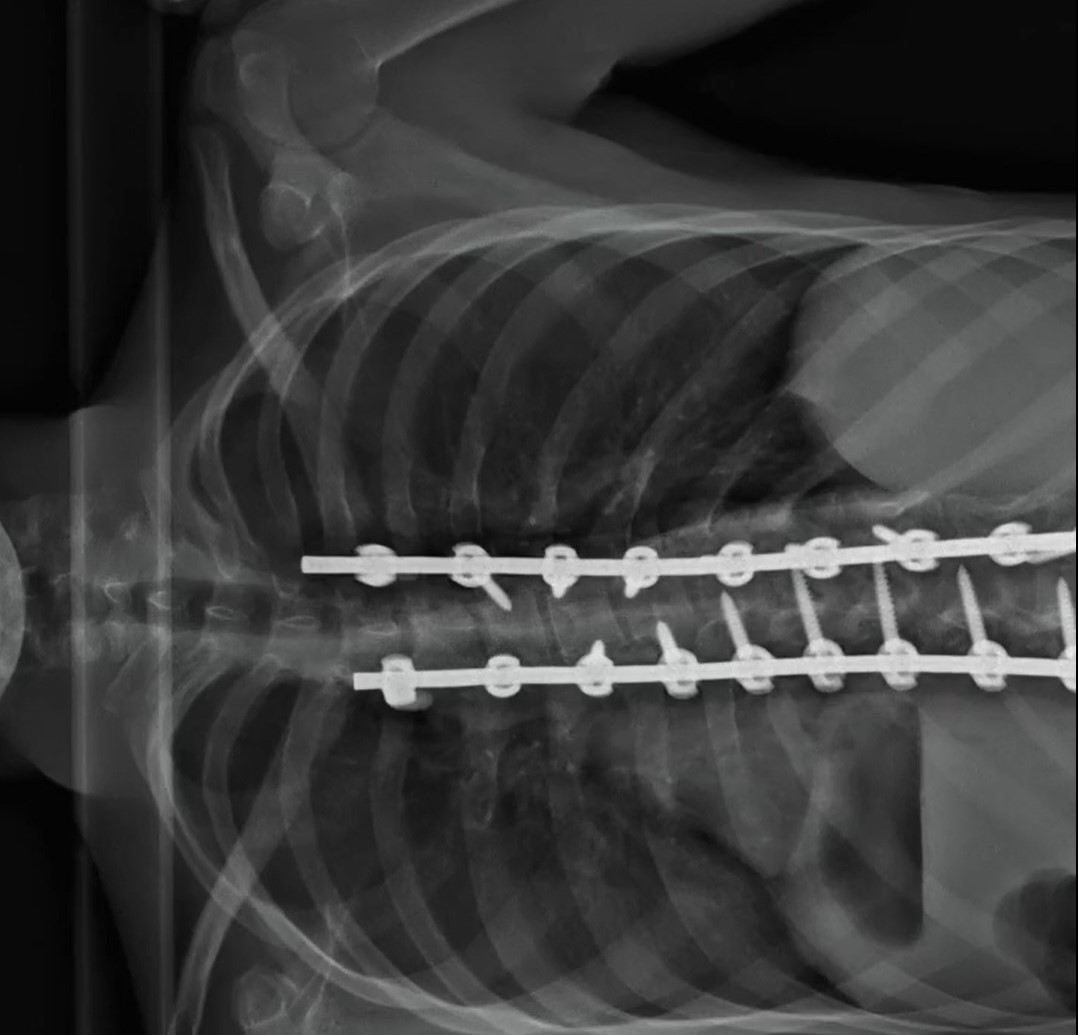

If you’re not cringing at the hammering and chiseling, drilling and screwing it takes to straighten a young man’s scoliosis, you’re made of sterner stuff than me. The eyeball poking and probing operation is but a warmup to the spinal surgery.